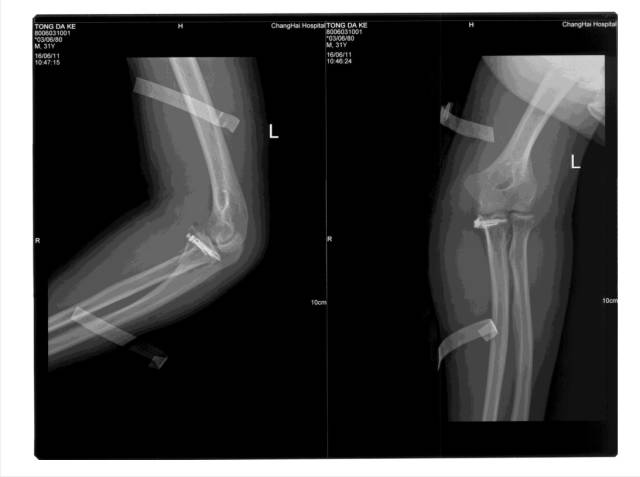

冠突是一个非常重要的稳定结构

• Ⅰ型和Ⅱ型单纯冠状突骨折,发生后方半脱位的风险很小,允许早期活动

• 即使单纯Ⅲ型骨折,在很小的生理应力下也有可能发生后方半脱位,特别是在屈肘60°~105°,支持对Ⅲ型损伤ORIF